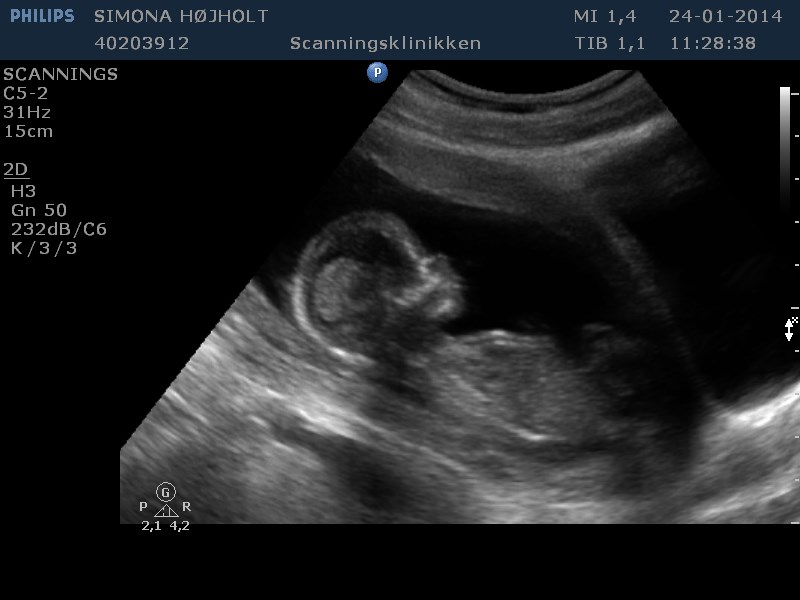

Ja, hvad skal vi have?

Svaret kender jeg, men kan I se det? ;-) Altid godt med lidt træning og gætterier!

Vedhæftede fotos (klik for at se i fuld størrelse)

Umiddelbart synes jeg at kunne se to streger på de nederste to billeder så jeg gætter på en pige